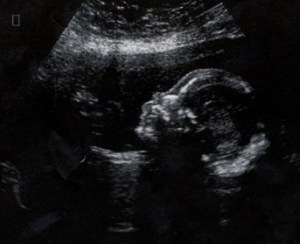

I first came across a picture of this young lad when I was researching CDG before we received a confirmed diagnosis. I was blown away by the similarities between him and my princess. Both have short long bones, feeding difficulties, and even the same cute little button noses. As this past year has gone by I’ve grown quite close to this fabulous family, exchanging gifts and often chatting online about our CDG type IIx wee ones throughout the week. To this day we are still amazed when we look at pictures, and have a very strong feeling that these two beautiful children may have the same undiscovered subtype.